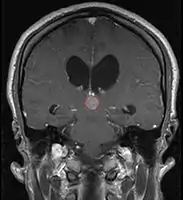

Pineal Gland Tumors

- Determined by the spatial anatomy and direction of growth

- Obstruction of aquaduct: hydrocephalus presenting as headaches, nausea, vomiting

- Compromise of superior colliculus: vertical gaze palsy, pupillary and oculomotor nerve paresis (Parinaud syndrome)

- Work-up includes MRI, CSF, serum markers for bHCG and AFP